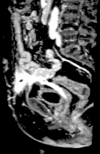

The management of enterocutaneous fistulas continues to be a challenging postoperative complication. Understanding the anatomy of the fistula optimizes its evaluation and management. Diagnostic radiology has always played an important role in this task. The use of plain radiography with contrasted studies and fistulograms is well documented in the earliest investigations of fistulas and they continue to be helpful techniques. The imaging techniques have evolved rapidly over the past 15 years with the introduction of cross-sectional imaging, ultrasound and endoscopy. The purpose of this chapter is to review both the diagnostic and therapeutic roles of fistulograms, small bowel follow-through, computed tomography, magnetic resonance imaging, ultrasound, and endoscopy in the setting of acquired enterocutaneous fistulas.